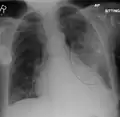

| A chest X-ray showing a very prominent wedge-shape bacterial pneumonia in the right lung | |